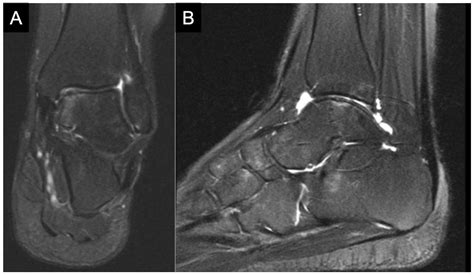

• Imaging Tests: Imaging tests, such as X-rays, MRI, or CT scans, are used to visualize the bone and cartilage within the ankle joint. These tests can help identify the location and extent of the lesion.

Imaging tests are particularly important in diagnosing Osteochondritis Dissecans Ankle, as they can provide detailed information about the condition of the bone and cartilage.